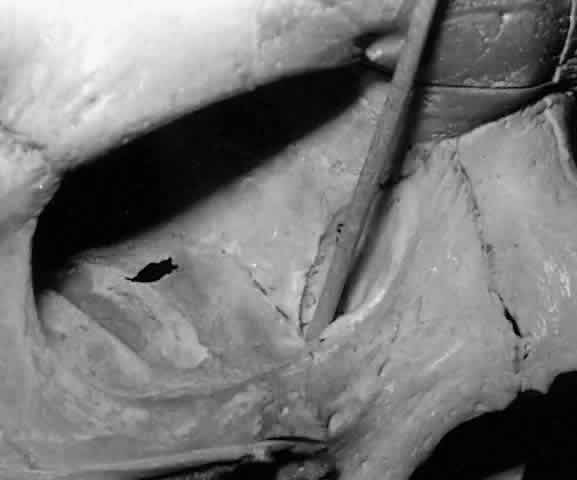

The canaliculi represent the palpebral portion of the lacrimal excretory system. The canaliculi conduct tears from the conjunctival fornix to the nasolacrimal sac. The initial 2 mm of each canaliculus is vertical, ending in a 1-mm dilation called the ampulla. The ampulla is located on the anterior side of the tarsus and is thus subjected to the compressive forces of the surrounding pretarsal orbicularis muscle. The initial course of the canaliculus is vertical and slightly anterior.2,19

At the ampulla, the canaliculus takes a horizontal course. Like the vertical portion, the horizontal portion of each canaliculus is surrounded by pretarsal orbicularis muscle fibers and is found close to the eyelid margin. Because the horizontal portion of the canaliculus follows the curved eyelid margin, it is not strictly horizontal. Medially, the horizontal canaliculus makes an anterior bend, entering the lacrimal sac nonperpendicularly.

The medial boundary of the lacrimal lake is formed by the plica semilunaris and the caruncle, which prevent apposition of the medial aspect of the eyelids with the eyeball. The longer lower canaliculus (10 mm) is directed into the lacrimal lake lateral to the plica semilunaris, while the shorter superior canaliculus (8 mm) collects fluid from the space between the plica semilunaris and the caruncle.2,18,19

Lining the lacrimal fossa and surrounding the lacrimal sac is a dense, fibrous membrane that Jones termed the lacrimal fascia.2 The upper and lower canaliculi narrow as they course medially to traverse the lacrimal fascia individually before they join, in the majority of cases, to form the common canaliculus (Fig. 19). The common canaliculus is located 2 to 3 mm posterior to the central portion of the medial canthal tendon. Histologically, the common canaliculus represents a diverticulum of the lacrimal sac and, if enlarged, is known as the sinus of Maier. The point of common canalicular entrance into the lacrimal sac is slightly above the midpoint of the sac on its lateral wall. In approximately 10% of cases, the upper and lower canaliculi can be found entering the lacrimal sac through separate openings, without the presence of a common canaliculus.20

Fig. 19. The upper and lower canaliculus, in the majority of cases, join to form the common canaliculus (pointer). The common canaliculus enters the lateral wall of the sac slightly above the midpoint of the sac.